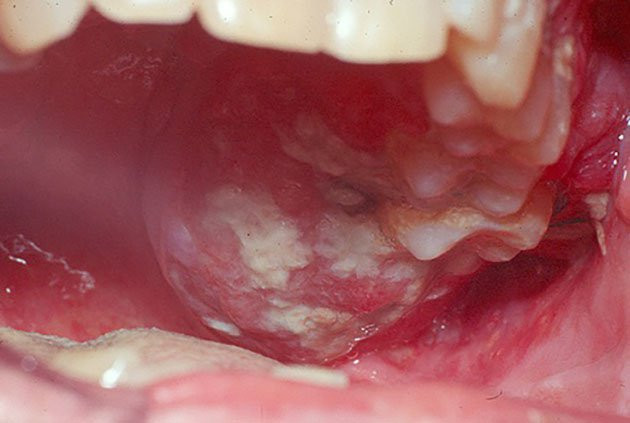

Đối với nhiều người, lở loét miệng là chuyện thường xuyên xảy ra. Nhiều khi chúng ta chỉ đơn giản là uống một số loại thuốc chống viêm, triệu chứng sẽ đỡ hẳn.

Tôi tin rằng đối với nhiều người, virus HPV còn tương đối xa lạ, nó thường ảnh hưởng đến cổ tử cung của chúng ta và dễ gây ung thư, nhưng bạn có biết không? Trên thực tế, nó vẫn là mối nguy hại lớn đối với khoang miệng của chúng ta.

Chúng ta thường nói rằng, hãy bổ sung cho cơ thể một số loại vitamin. Thực tế, chúng ta thường chỉ chú ý đến vitamin C hoặc B, nhiều người bỏ qua tầm quan trọng của vitamin A. Điều này vô tình gây ra nhiều tổn thương cho các mô biểu mô bên trong cơ thể chúng ta, nhiều khả năng gây ung thư, đặc biệt là ung thư miệng.